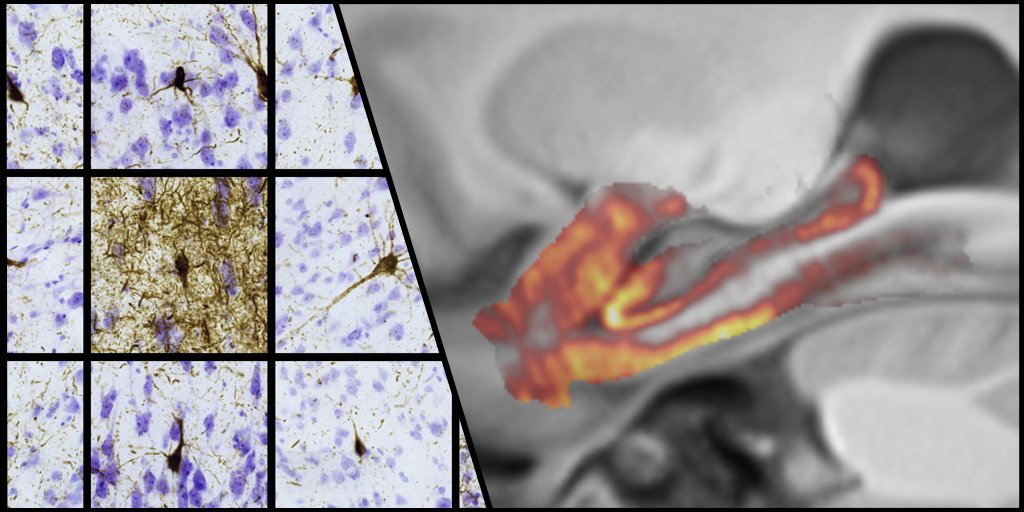

Yushkevich et al. use MRI and dense serial histology to construct the first three-dimensional maps of tau neurofibrillary tangle pathology at individual and group levels. bit.ly/3khw5Ek